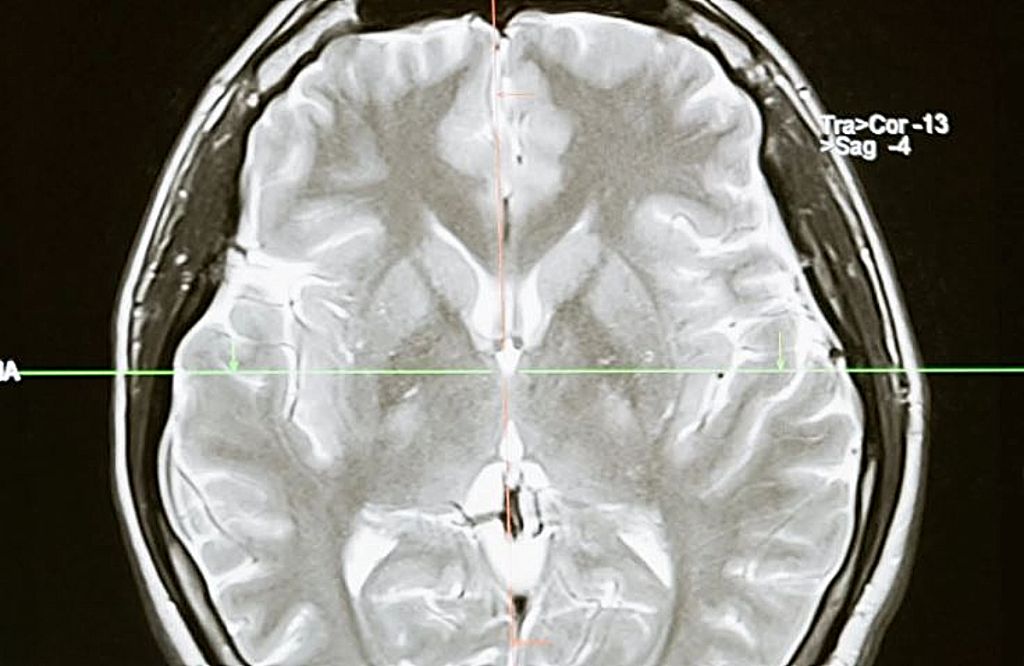

Covid-19 : Όσοι είχαν μακροχρόνια συμπτώματα υποφέρουν κατά 81% από επίμονα νευρολογικά προβλήματα

Η Northwestern Medicine αναφέρει ότι το 85% που νόσησαν από Covid αλλά δε νοσηλεύτηκαν στα νοσοκομεία, υποφέρουν από επίμονα νευρολογικά προβλήματα, όπως «νεφελώδη» εγκέφαλο, κεφαλαλγία και μούδιασμα ή μυρμήγκιασμα.

Τα προβλήματα αυτά επηρεάζουν τη μεγάλη πλειονότητα των ασθενών Covid-19 που δεν ήταν ποτέ αρκετά άρρωστοι για να νοσηλευτούν, σύμφωνα με μελέτη που δημοσιεύθηκε την Τρίτη στο Annals of Clinical and Translational Neurology.

Η έρευνα, από τη Northwestern Medicine στο Σικάγο, βασίζεται σε μια ανάλυση 100 ασθενών που είχαν συμπτώματα Covid-19 για μεγάλο χρονικό διάστημα και των οποίων τα συμπτώματα έχουν διαρκέσει τουλάχιστον έξι εβδομάδες. Όλοι είχαν αρχικά μια ήπια ασθένεια: πονόλαιμο, βήχα, χαμηλό πυρετό.

Αλλά μετά το διάστημα που είχαν συμπτώματα οξείας λοίμωξης, το 85% ανέφερε τουλάχιστον τέσσερα διαρκή νευρολογικά προβλήματα που έχουν επηρεάσει την καθημερινή τους ζωή.

Μέχρι στιγμής, το πιο συχνά αναφερόμενο σύμπτωμα ήταν ο «νεφελώδης εγκέφαλος», με το 81 τοις εκατό των ερωτηθέντων να αναφέρει τρέχοντα προβλήματα με τη μνήμη και τη σκέψη.

68% δήλωσε ότι είχε πονοκεφάλους και περισσότεροι από τους μισούς δήλωσαν ότι είχαν προβλήματα με την απώλεια γεύσης και μυρωδιάς, μούδιασμα ή μυρμήγκιασμα και μυϊκό πόνο.